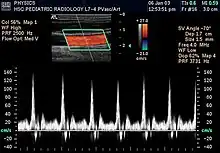

L'échographie Doppler est un examen médical échographique en deux dimensions non invasif qui permet d'explorer les flux sanguins intracardiaques et intravasculaires. Elle est basée sur un phénomène physique des ultrasons : l'effet Doppler. Elle est souvent surnommée écho Doppler.

Les modes de représentation des signaux recueillis par réflexion sont de plusieurs types[5] :

Les échographes Doppler actuels permettent un codage couleur des flux sanguins. Par convention, les flux positifs qui s'approchent de la sonde sont codés en rouge, les flux qui s'en éloignent sont codés en bleu. Il permet ainsi une visualisation directe des flux sanguins qui se superposent à l'image en échographie bidimensionnelle en échelle de gris.